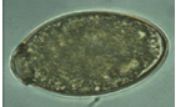

The egg in the image is of _____ and it is treated by praziquantel (5–10 mg/kg once)